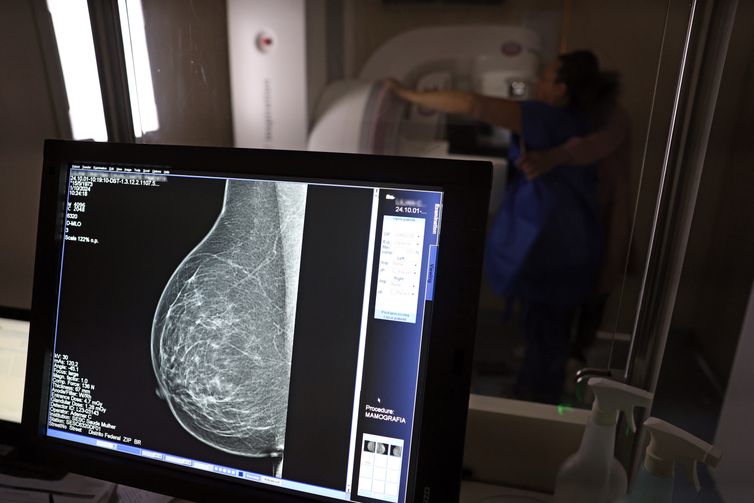

Câncer de mama: uma em cada três pacientes tem menos de 50 anos

Dados do Painel Oncologia Brasil, analisados pelo Colégio Brasileiro de Radiologia e Diagnóstico por Imagem (CBR), indicam que mais de 108 mil mulheres com menos de 50 anos foram diagnosticadas com câncer de mama no Brasil no período entre 2018 e 2023 – uma média de uma em três mulheres diagnosticadas com a doença.

Para a entidade, os números reforçam a importância de ampliar o rastreamento do câncer de mama por meio da realização de mamografia em mulheres abaixo dos 50 anos e acima dos 70 anos, faixas etárias que não estão incluídas na recomendação padrão de exames preventivos no âmbito do Sistema Único de Saúde (SUS). >> Siga o perfil da Agência Brasil no Instagram